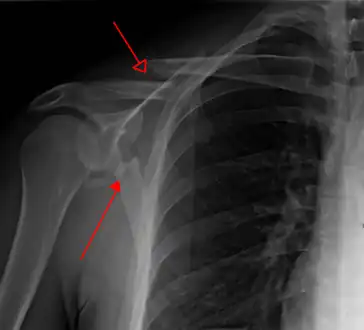

Most fractures of the scapula can be seen on a chest X-ray; however, they may be missed during examination of the film.[1] Serious associated injuries may distract from the scapular injury,[4] and diagnosis is often delayed.[3] Computed tomography may also be used.[1] Scapular fractures can be detected in the standard chest and shoulder radiographs that are given to patients who have had significant physical trauma, but much of the scapula is hidden by the ribs on standard chest X-rays.[4] Therefore, if scapular injury is suspected, more specific images of the scapular area can be taken.[4]

X-ray showing a fracture of the clavicula and scapula